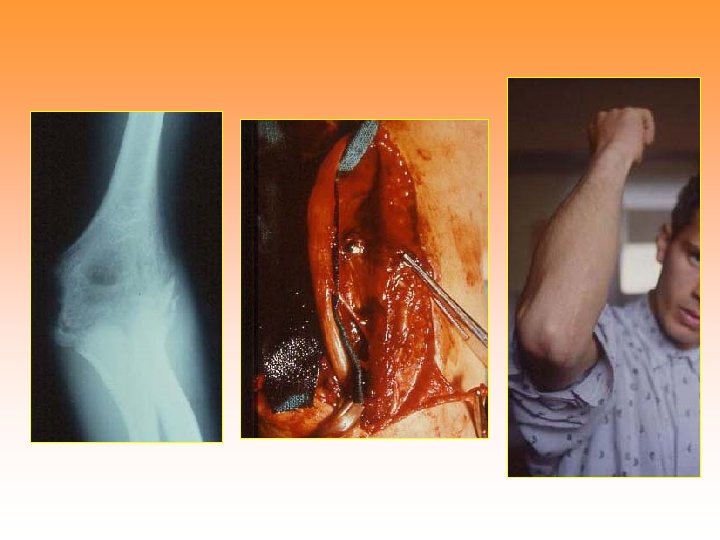

Epiphiseal trauma of the throclea • Salter Type V • Varus deformity of the elbow Ulnar nerve compression Children: Vedge osteotomy Adult: Ulnar nerve transposition

Anterior traslocation of the ulnar nerve Surgical technique